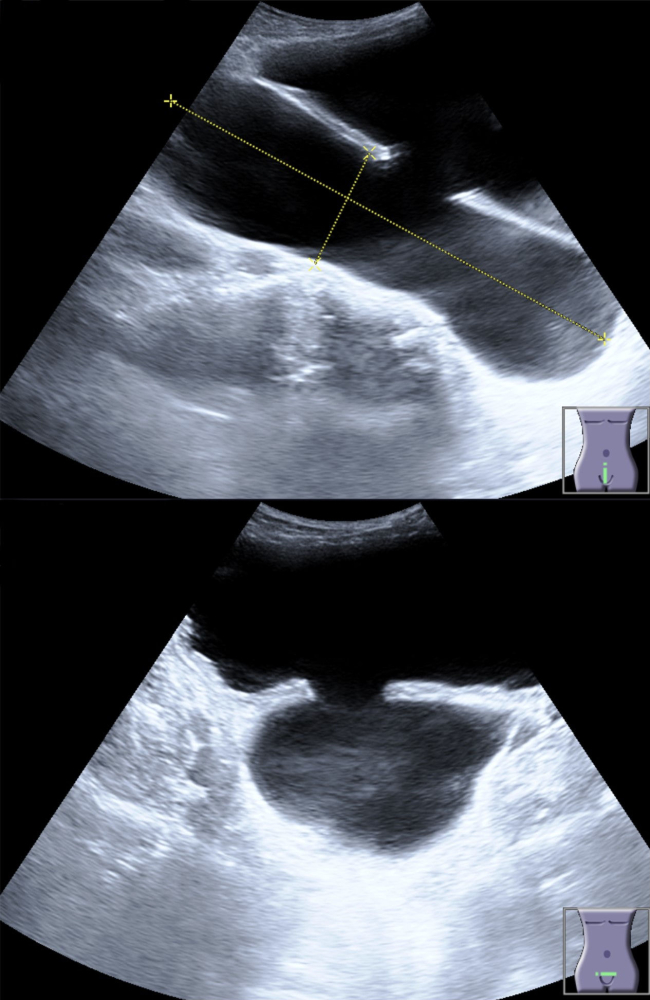

If the bladder cells are weak, bladder tissues can get red, inflamed, and irritated. Inside the bladder, tissues are rough and convoluted. When these tissues get inflamed, it’s easy for bacteria and other infectious pathogens to get trapped and cause inflammation and irritation that can’t easily be treated using antibiotics from the doctor’s office.Indeed, some people are born with bladder diverticulum or little pouches in the bladder wall where urine, bacteria, and other pathogens can easily colonize the bladder. Other people who are not born with this issue can develop bladder diverticulum in response to any number of bladder tissue insults. A bladder diverticulum can act as a “reservoir” where urine gets stored even after the patient has attempted to fully empty the bladder. A reservoir of this sort can often be emptied fully during urination by simply urinating, then standing up and moving around to get all remaining urine moving toward the urethra, and then sitting down to urinate again. This simple act of emptying a urinary reservoir, whether it is caused by bladder diverticula or by inflammation of other organs such as the intestines (which can put pressure on the bladder such that it causes urine retention), can be life-changing in terms of its ability to get rid of recurrent UTIs and reduce cystitis inflammation and irritation.

The bladder can sometimes develop "diverticulum" which are pockets or outgrowths where urine can be stored as a reservoir and bacteria grow to cause cystitis or recurrent urinary tract infections.